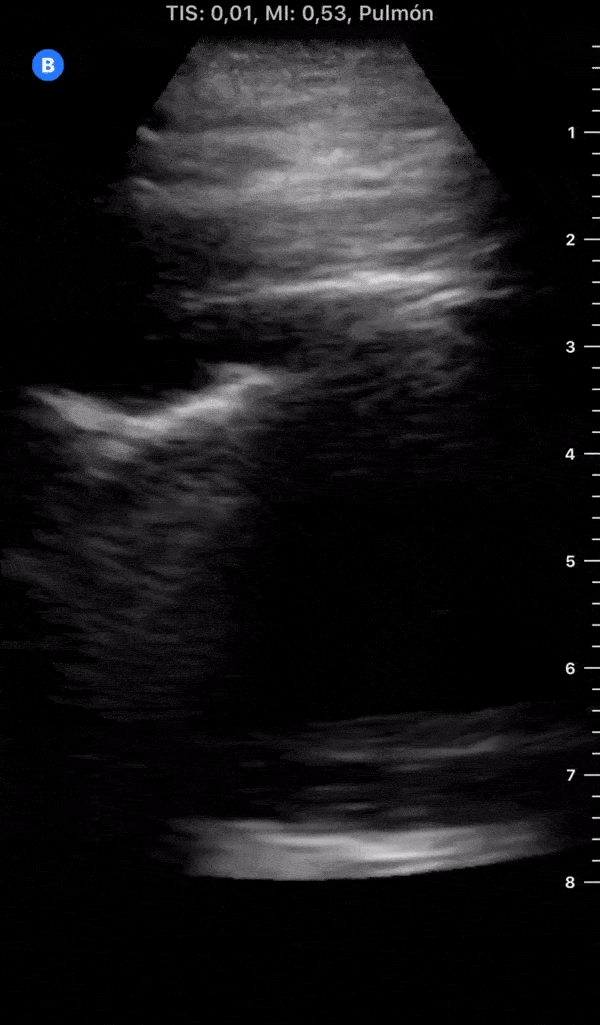

COVID 19 Lung US Disease Progression - Day 3

Day 3 after #COVID diagnosis. No sore throat/headache. Yesterday was cough day, still no shortness of breath/chest pain. Diarrhea started, lucky cough got better. #POCUS update: similar effusion, seems less thickened pleural line + no b-lines (PLAPS). @yaletung